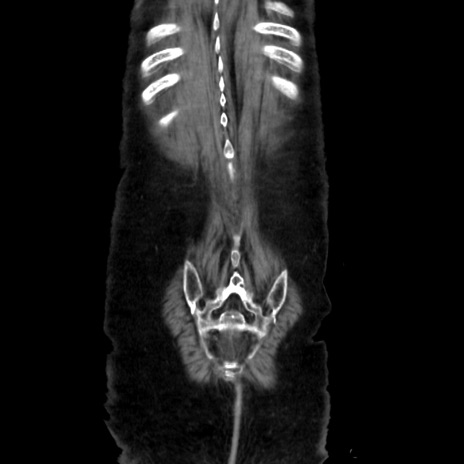

症例40(冠状断像)

矢状断像